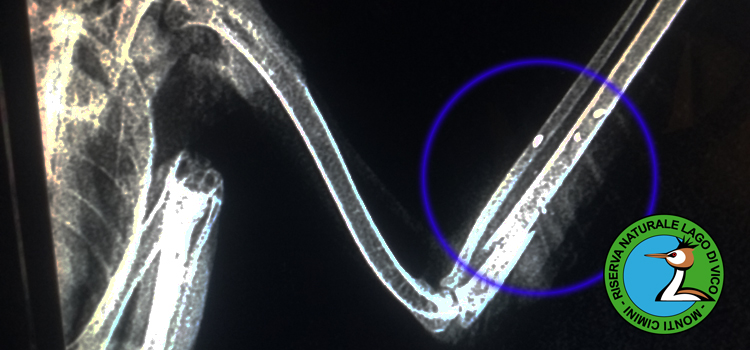

Sono stati ricevuti al CRAS una femmina adulta di falco pellegrino proveniente da Anzio (Rm) e un giovane maschio di aquila minore da Celleno (Vt) e un giovane sparviere da Carbognano (Vt). Tutti e tre i rapaci, specie protette a livello internazionale, erano stati colpiti da colpi d'arma da fuoco: i primi due animali presentavano fratture alle ali e sono stati presi in cura presso il la struttura della Riserva Lago di Vico. Lo sparviere è purtroppo morto poco dopo l'arrivo a causa delle gravissime ferite riportate.